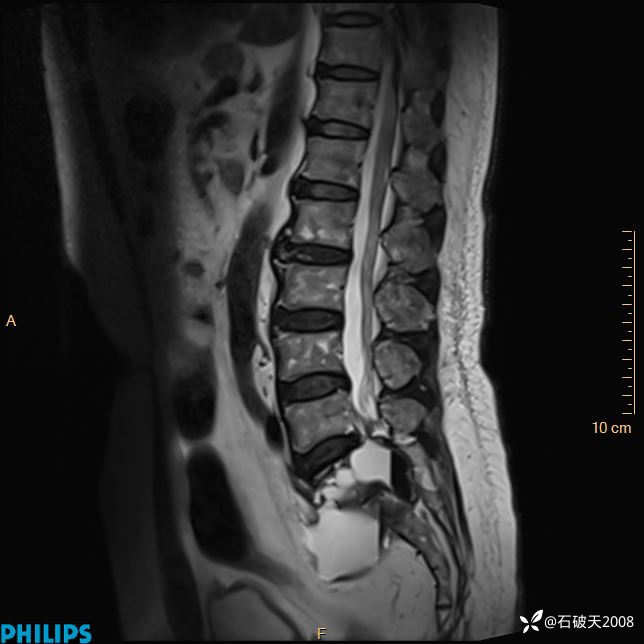

2023年3月份MRI影像

T2矢状位